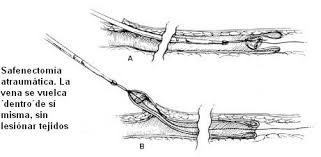

231 × 397 - gimolimpo.com

{"cl":3,"id":"Ofxp5Rburirp3M:","isu":"gimolimpo.com","itg":0,"ity":"jpg","oh":397,"ou":"http://www.gimolimpo.com/Paginas/feblectomia_archivos/image005.jpg","ow":231,"pt":"FEBLECTOMIA","rid":"ZemkA-aU5uHAnM","rmt":0,"rt":0,"ru":"http://www.gimolimpo.com/Paginas/feblectomia.htm","s":"Flebectomía

ambulatoria, es la safenectomía, modificada por el Dr. Oesch, suizo,

que consiste en efectuar la exéresis de la vena, sin lesionar los

tejidos

...","sc":1,"st":"Olimpo","th":294,"tu":"https://encrypted-tbn0.gstatic.com/images?q\u003dtbn:ANd9GcQTaZ5oRKfEvwuBOC5RWCE4GIQU2e4MrfYhpJMx2vBMlbt5qVXNew","tw":171}